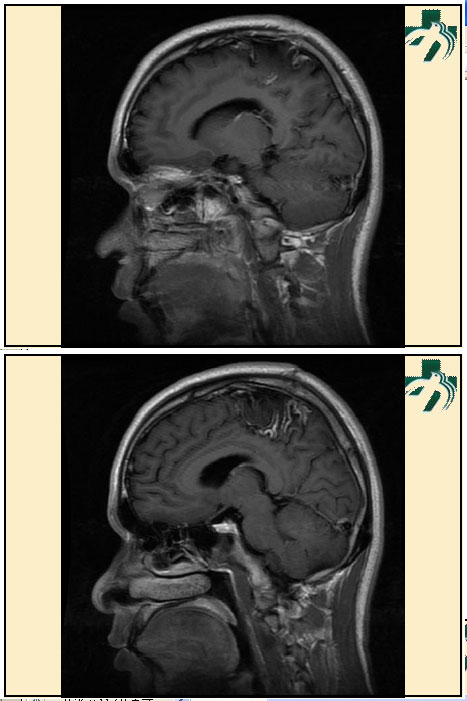

奴卡氏菌感染

第九期三博

读片会

病例之四

北京协和医院 提供

男性,22岁。自觉虫咬后皮疹、肢体麻木4月